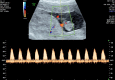

The placenta is the largest fetal organ, and toward the end of pregnancy the umbilical circulation receives at least 40% of the biventricular cardiac output. It is not surprising, therefore, that there are likely to be close haemodynamic links between the development of the placenta and the fetal heart. Development of the placenta is precocious, and in advance of that of the fetus. The placenta undergoes considerable remodeling at the end of the first trimester of pregnancy, and its vasculature is capable of adapting to environmental conditions and to variations in the blood supply received from the mother. There are two components to the placental membranes to consider, the secondary yolk sac and the chorioallantoic placenta. The yolk sac is the first of the extraembryonic membranes to be vascularized, and condensations in the mesenchyme at ~17 days post-conception (p.c.) give rise to endothelial and erythroid precursors. A network of blood vessels is established ~24 days p.c., with the vitelline vein draining through the region of the developing liver into the sinus venosus. Gestational sacs of early pregnancy failures often display aberrant development of the yolk sac, which is likely to be secondary to abnormal fetal development. Vasculogenesis occurs in the villous mesenchyme of the chorioallantoic placenta at a similarly early stage. Nucleated erythrocytes occupy the lumens of the placental capillaries and end-diastolic flow is absent in the umbilical arterial circulation throughout most of the first trimester, indicating a high resistance to blood flow. Resistance begins to fall in the umbilico-placental circulation around 12-14 weeks. During normal early pregnancy the placental capillary network is plastic, and considerable remodeling occurs in response to the local oxygen concentration, and in particular to oxidative stress. In pregnancies complicated by preeclampsia and/or fetal growth restriction, utero-placental malperfusion induces smooth muscle cells surrounding the placental arteries to dedifferentiate and adopt a proliferative phenotype. This change is associated with increased umbilical resistance measured by Doppler ultrasound, and is likely to exert a major effect on the developing heart through the afterload. Thus, both the umbilical and maternal placental circulations may impact on development of the heart.